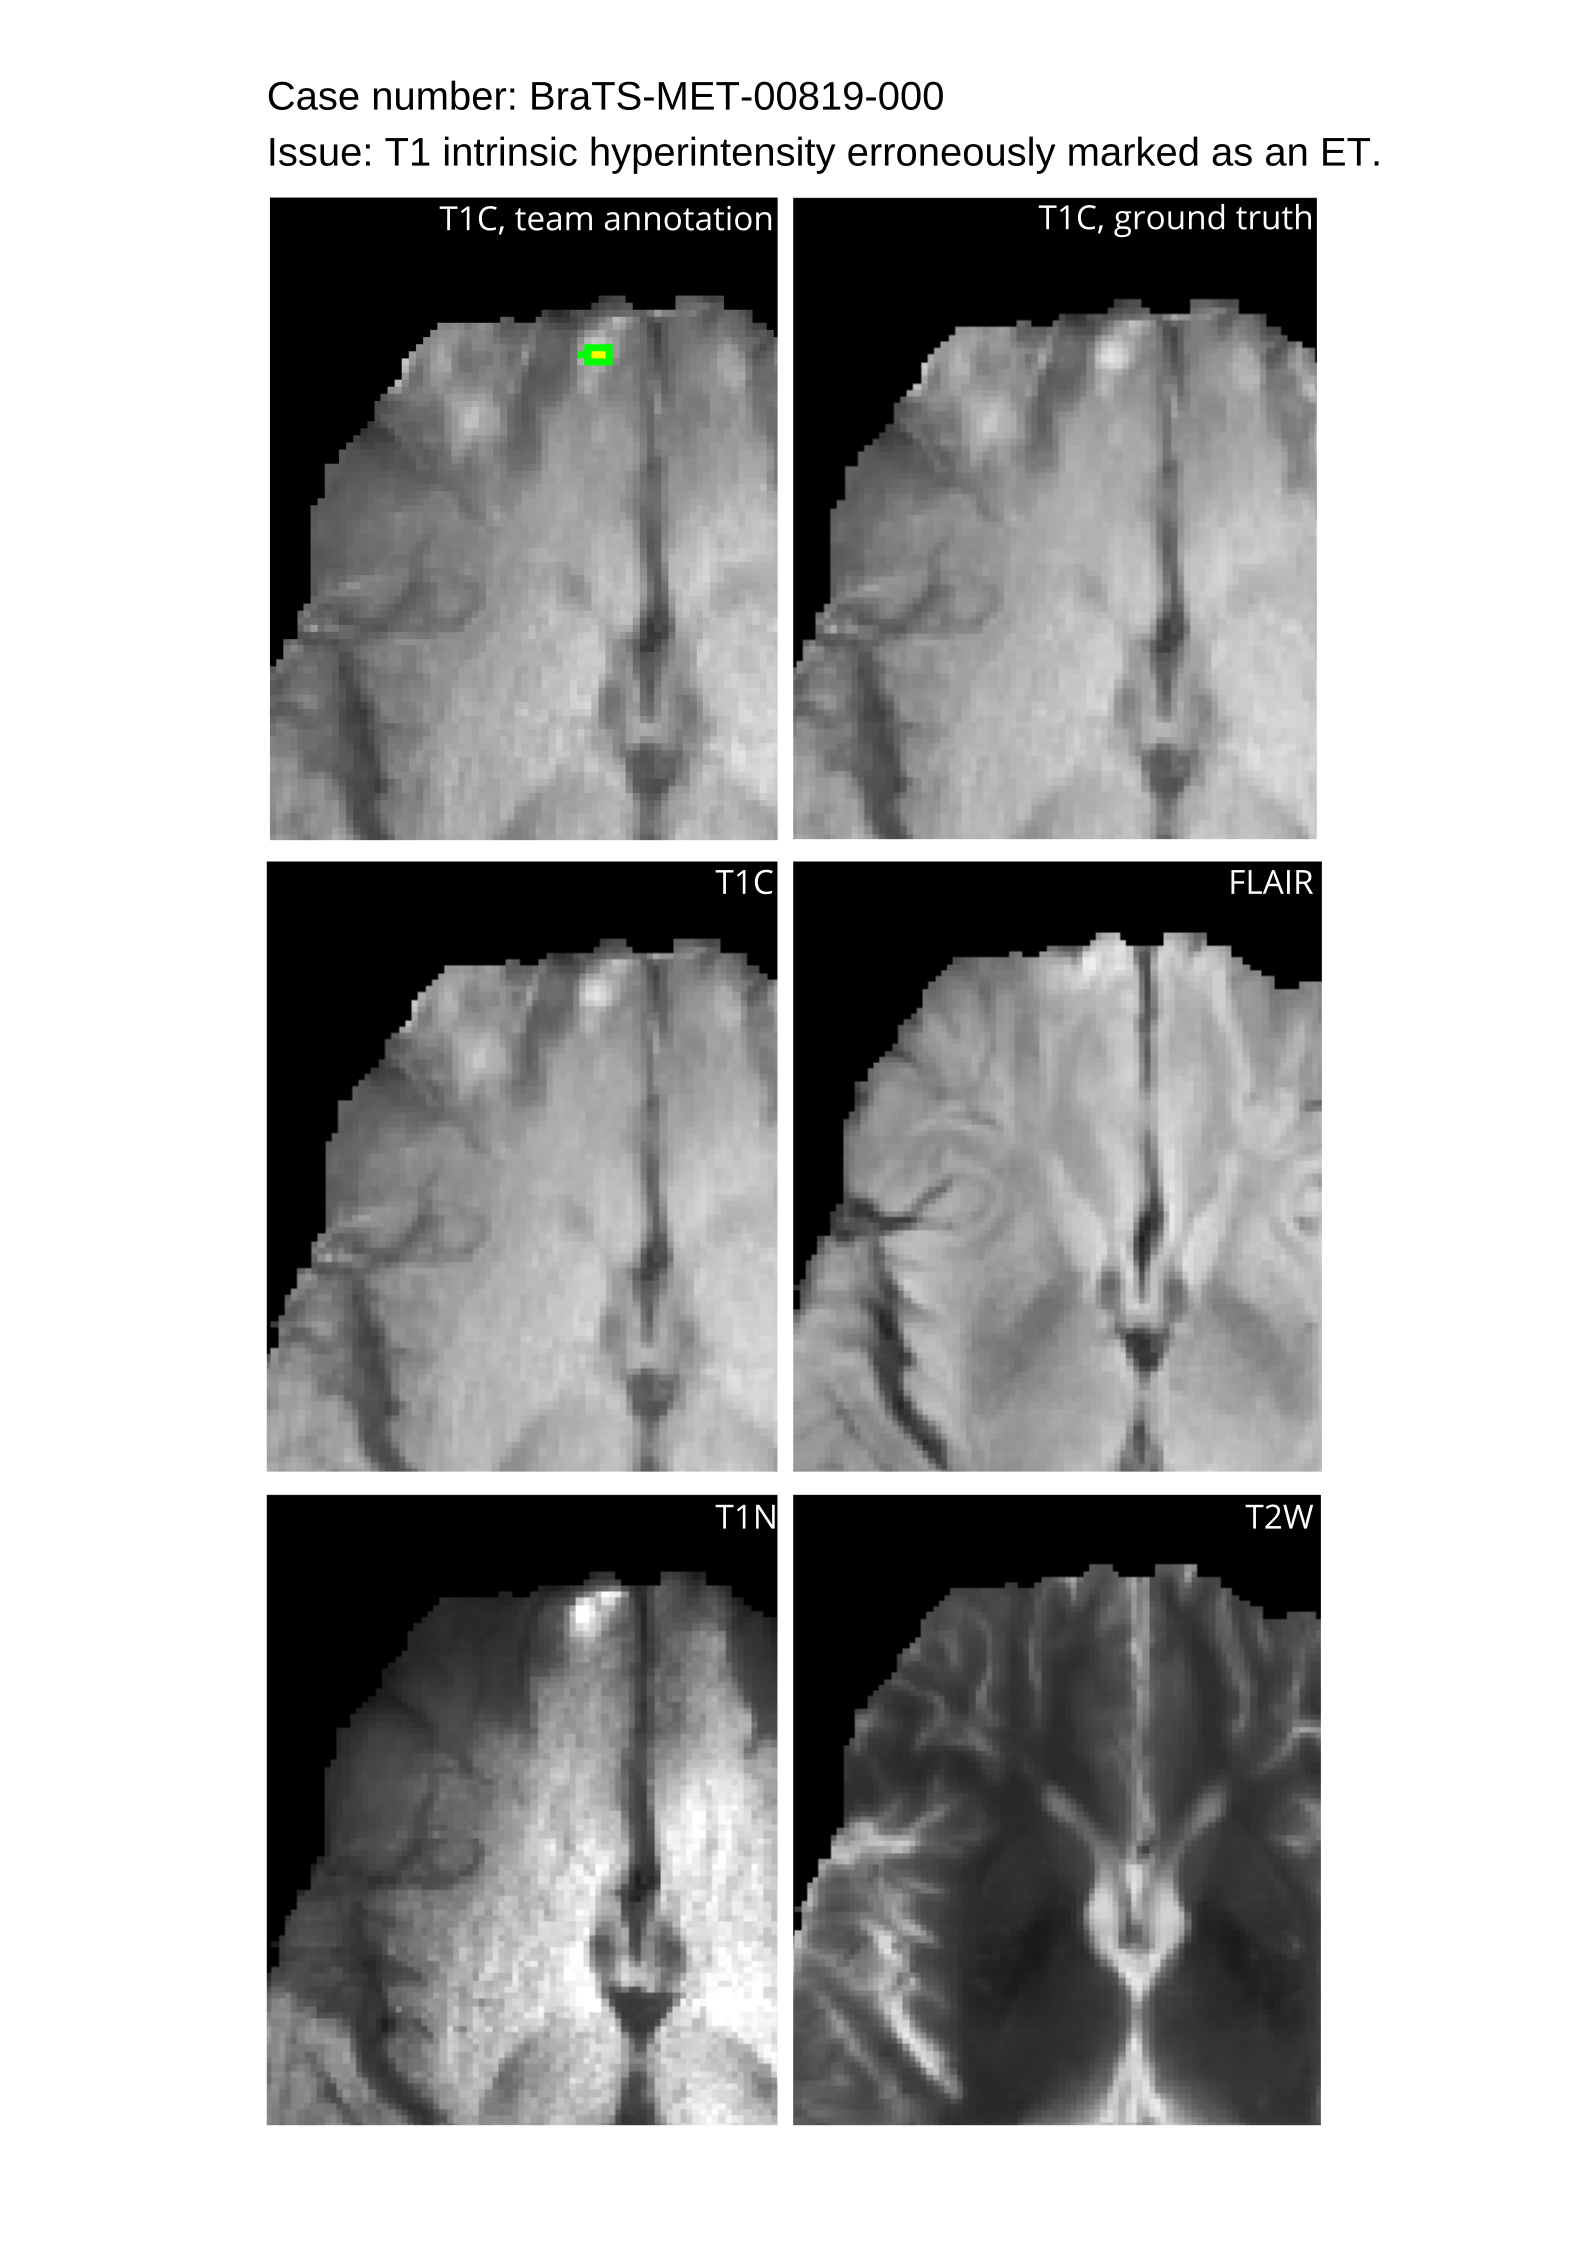

Approvers reviewed the volunteer annotations and either approved the case or returned it to students for re-annotation. Additionally, a QC process was implemented, which included removing all random voxels and any voxels outside the brain mask, ensuring all images had the same parameters (space, orientation, and origin) as the SRI24 atlas, and verifying the presence of all segmentations and segmentation masks are in the folder with original NIfTI images.

4.9 Common Errors of Automated Segmentations

Based on observations from previous BraTS challenges, common errors in automated segmentations were identified. The most typical errors in the current challenge included:

1. 1.

Automated algorithms missing small metastases. Enhancing metastasis was fused using the minority voting algorithm to aggregate all enhancing tumor voxels identified by the three algorithms. However, many small metastases were missed and were manually segmented by neuroradiology attendings.

2. 2.

Segmentation of white matter changes from microvascular disease. Peritumoral edema segmentations were checked by neuroradiology attendings and modified.

3. 3.

The segmentation of non-enhancing lesions that have intrinsic T1 hyperintensity. Voxels with intrinsic T1 hyperintensity were manually removed from ET segmentations.

These insights led to specific adjustments in the annotation process to enhance accuracy.